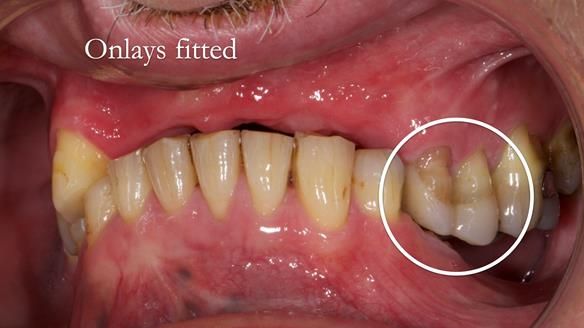

2. Onlay preparations: Composite onlays were fitted for his upper left premolars to repair these teeth and support the new denture.

Keith’s denture incorporated a Duracetal shell clasp on upper right first premolar (Myerson), which are designed to be virtually visible, providing a more aesthetic solution while enhancing patient comfort. The Scandinavian-inspired approach, based in modern removable prosthodontic techniques, ensured the denture was not only durable but also visually pleasing. Additionally, the design was carefully planned to allow for future modifications, ensuring that if Keith loses additional teeth, the denture can be adapted rather than replaced entirely.